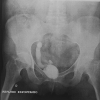

Results: Patient 1: A 58-year-old female had five episodes of acute left ureteral lithiasis in two years prior to left kidney tuberculosis. Patient 2: A 55-year-old male patient had a 1.2 cm proximal left ureteral stone and in the following six months, the diagnosis of tuberculosis was made in a nonfunctioning left kidney with ureteral thickening and stenosis. Patient 3: A 47-year-old male patient had a 1.2 cm stone in the proximal right ureter and developed urinary tuberculosis with a nonfunctioning right kidney and a contracted bladder.